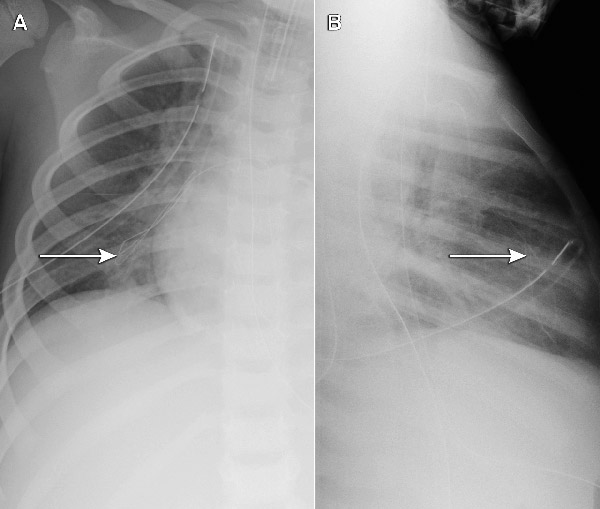

Each of the five cases identified was undetected at the time of insertion. As only part of the guide wire embolised, the portion withdrawn by the operator provided a false reassurance. The extremely fine embolised wires had not been noted on post-insertion chest x-rays (where the focus is usually on the position of the catheter tip), but were apparent when a specific review of the films was undertaken (Box 2). This cluster of five cases (involving different operators) at a single hospital triggered a statewide case review, through which an additional five cases in two further hospitals were reported (one actual embolus and four “near misses”, where the wire unravelled, but was noticed and retrieved before entering the patient). All involved the same type of device, giving a total of 10 cases at three hospitals out of 710 patients followed up. Although objective data about whether the wire was cut in every case were not available (because it can be cut without detection), at least one clinician was certain the wire had not been cut.

The sentinel event in this case series was the incidental identification of a fine filament of wire on chest x-ray after insertion of a 3 Fr PICC in a 4-year-old child in June 2008. The outer coiled covering of the guide wire had delaminated and separated from the inner core. Computed tomography confirmed a metallic wire within the right ventricle and extending into a pulmonary artery. The embolised wire was removed by cardiac catheterisation.